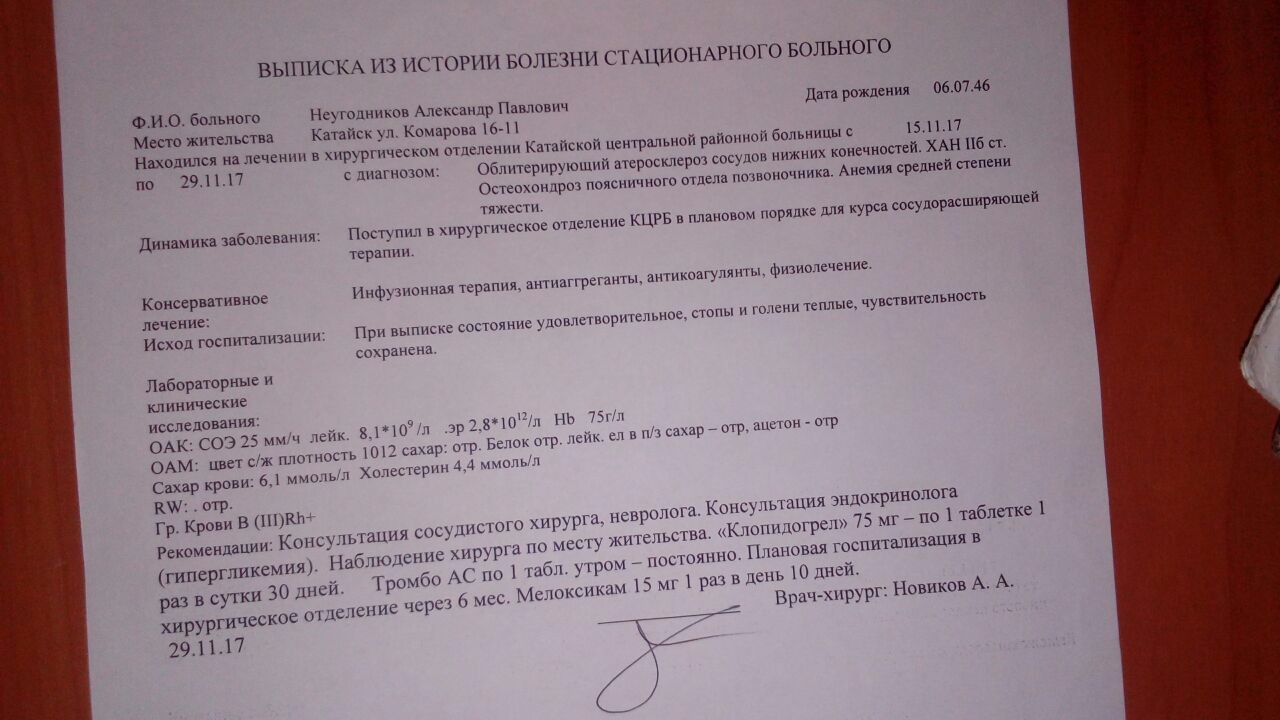

Изображения, связанные с атеросклерозом нижних конечностей и его лечением